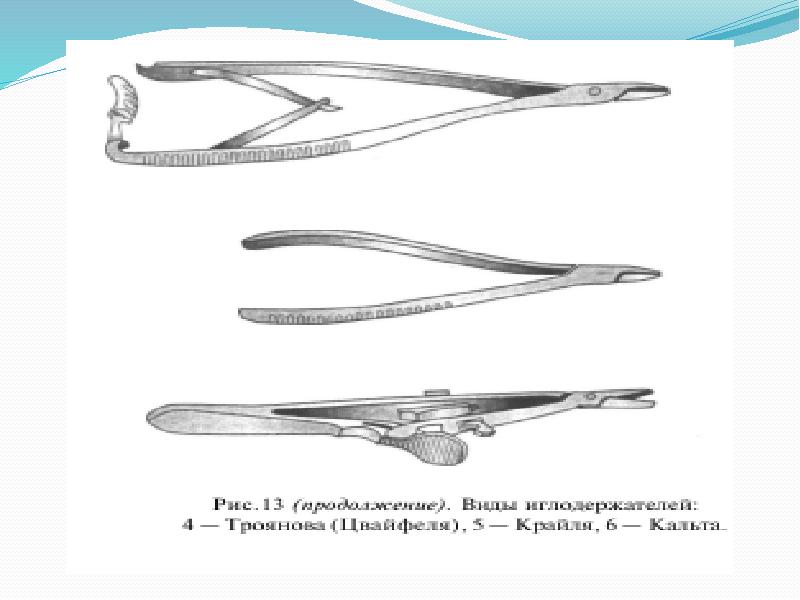

- 4. Иглодержатели Иглодержатель Гегара

- 5. Иглодержатель Матье Иглодержатель Матье

- 7. Иглодержатель Кастровьехо Иглодержатель Кастровьехо